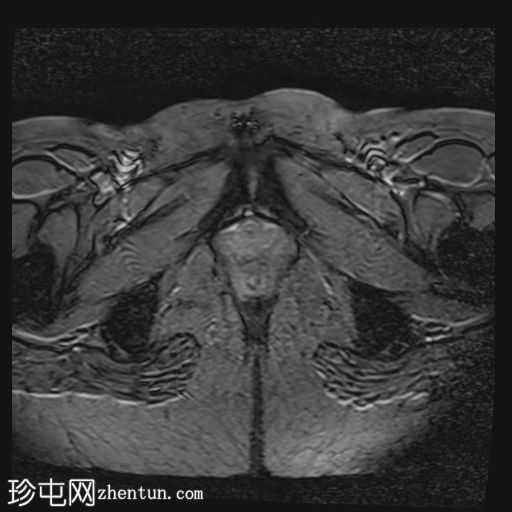

轴位

T2血流加权像

MRI特征符合剖宫产术后瘢痕子宫内膜异位症,表现为特征性T1高信号伴T1FS持续存在,T2低信号伴内部高信号灶,病灶边缘浸润于腹前壁肌肉内,以及对比增强。

该病灶累及腹白线并浸润腹直肌,主要位于中线左侧,耻骨联合及结节处腹直肌起点上方。

影像学表现符合病灶内出血成分,提示既往剖宫产瘢痕处存在异位子宫内膜组织。